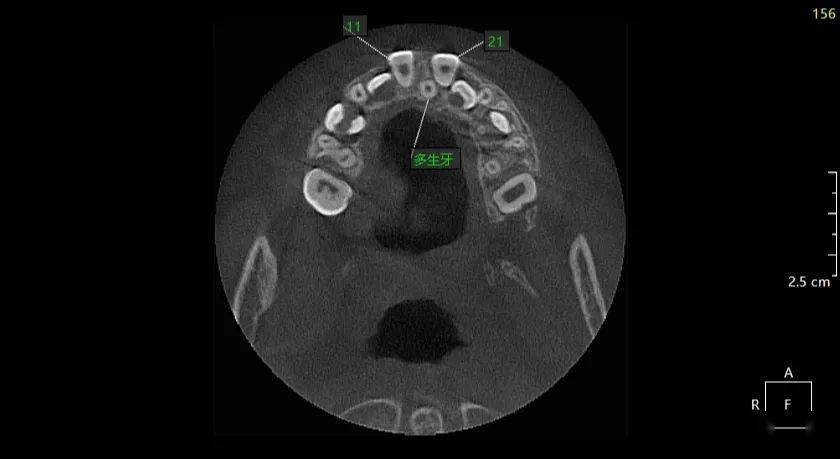

朱xx 20210417 多生牙cbct 131xxxx8088

图片尺寸840x388